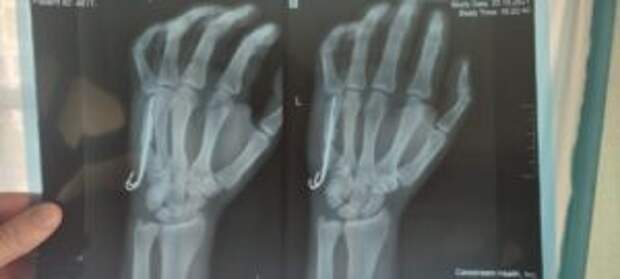

Am Montag, dem 07.03.22, kommt der erste Verletzte zur Behandlung in München an. Hier ist eine Zusammenfassung des Patienten: Diagnose: Schussfraktur des fünften Mittelhandknochens mit Dislokation. Es entstand ein falsches Gelenk, eine Operation ist erforderlich. Aufnehmendes Krankenhaus: Universitätsklinikum Rechts der Isar.

Diagnose: Schussfraktur des fünften Mittelhandknochens mit Dislokation. Es entstand ein falsches Gelenk, eine Operation ist erforderlich.